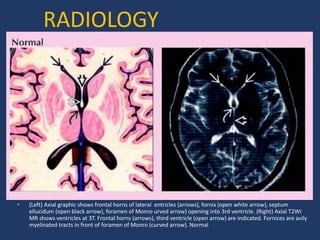

• (Left) Axial graphic shows frontal horns of lateral entricles (arrows), fornix (open white arrow), septum

ellucidum (open black arrow), foramen of Monro urved arrow) opening into 3rd ventricle. (Right) Axial T2WI

MR shows ventricles at 3T. Frontal horns (arrows), third ventricle (open arrow) are indicated. Fornices are avily

myelinated tracts in front of foramen of Monro (curved arrow). Normal